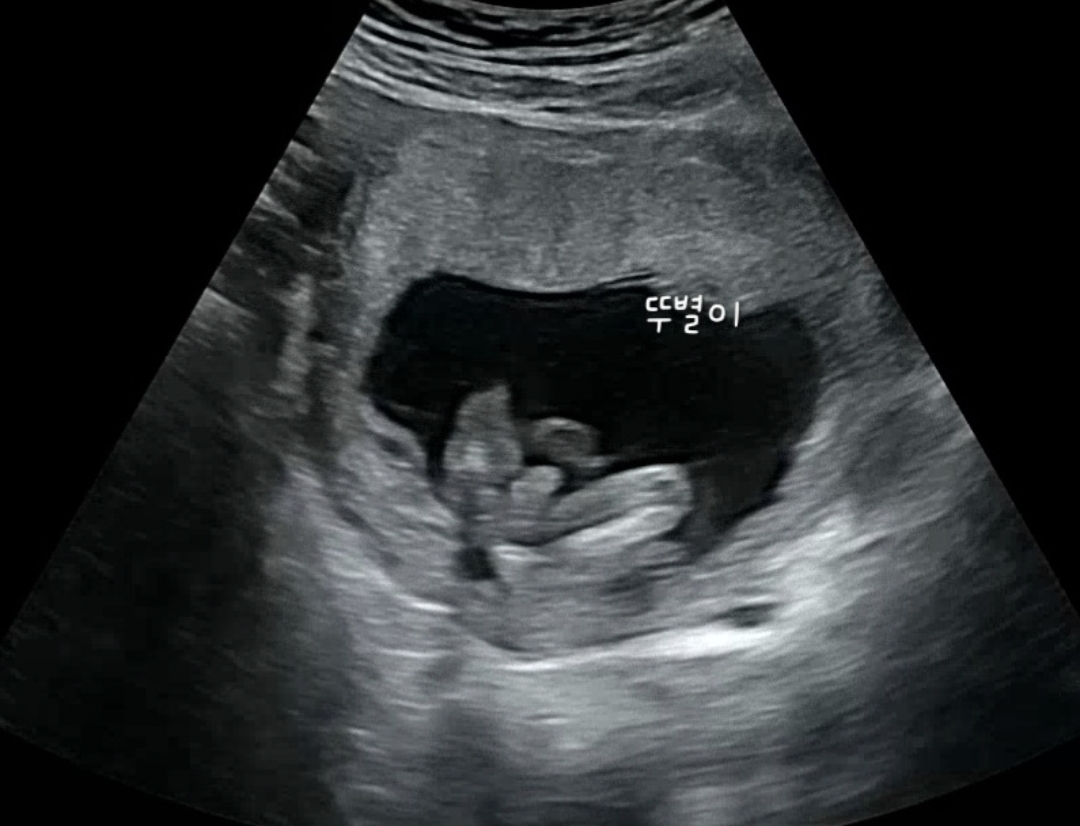

12주 15주 초음파 - 남아 확정

평소 있던 미주신경실신 때문에 어제 쓰러지기 직전까지 또 가서 걱정되는 마음에 병원에 들렸어요. 12주차에 남아인 것 같다는 느낌이 들었는데 15주차가 된 어제, 남아 확정을 받았네요 ㅋㅋㅋㅋㅋㅋㅋㅋ 선생님이 남아라고는 안 하셨는데 '뭔가 잘 보셨죠?'라며 힌트를ㅋㅋㅋㅋㅋ